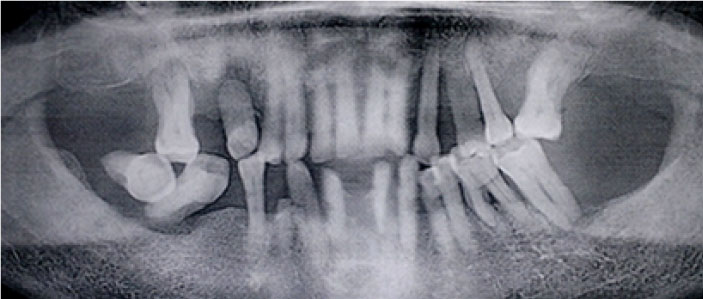

Figure 2.

A panoramic x-ray of the patient presented in Figure 1. Note severe generalized radiographic bone loss extending to the middle or apical third of the root.

Periodontal clinical characteristics are described in Table 2. The plaque index (PI) value was 78.9±19.1%, and the mean bleeding on probing (BOP) was 57.2±21.6%. The prevalence rates of stage I/II periodontitis and stage III/IV periodontitis were 37.42% and 62.58%, respectively. The prevalence of localized periodontitis (LP) and generalized periodontitis (GP) was 60.23% and 39.77%, respectively. PD ≥6 mm was present in 47.15% of the sample. One-third (34.90%), one-quarter (25.50%), and two-thirds (64.77) of patients had gingival recession, mobile teeth, and missing teeth, respectively. Radiographically, horizontal bone lysis (33.39%) and mixed bone lysis (41.11%) were the most observed (Figures 1 and 2) (Table 2).